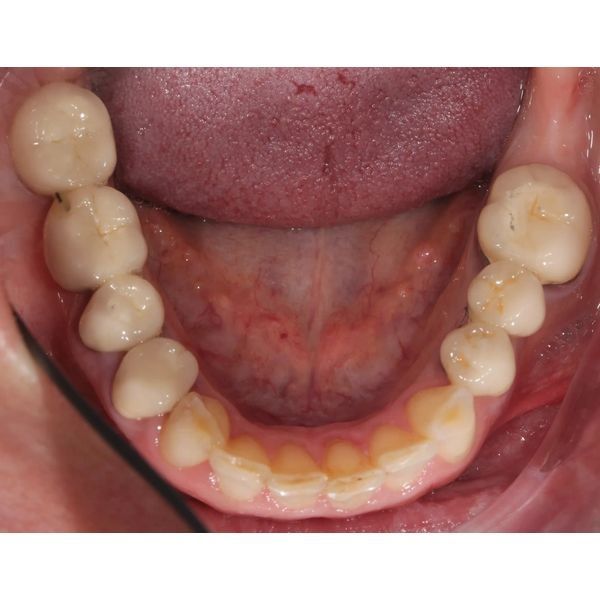

При осмотре выяснилось, что конструкции на центральных зубах хоть и выглядели эстетично, на них появились трещины и сколы, было нарушено краевое прилегание. Кроме того, у женщины наблюдалась стираемость зубов, особенно заметно стёрся нижний клык (зуб 3.3). На других зубах также присутствовали сколы.

Десневой контур был неровным, а сама десна в ряде участков выглядела нездоровой, что могло быть вызвано краевым прилеганием конструкций и неидеальной гигиеной.

Жевательные поверхности боковых зубов оставались гладкими. Это говорило о том, что у пациентки не было окклюзионных помех, которые могли бы спровоцировать проблемы с височно-нижнечелюстным суставом (ВНЧС), однако из-за отсутствия рельефа контакт между зубами-антагонистами плоскостной, а не точечный, поэтому мышцам приходилось прилагать больше усилий, чтобы пережевать пищу.